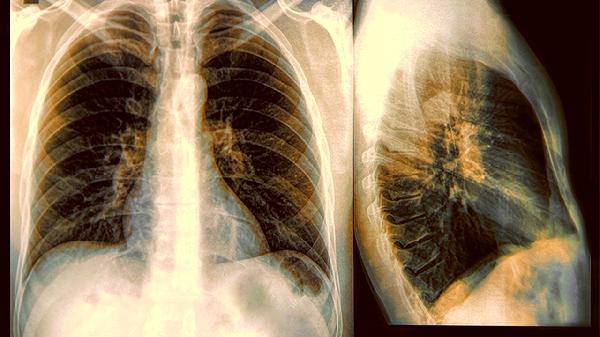

1.呼吸模式改变

从规律呼吸逐渐变成潮式呼吸,就像海浪一样有起伏间隔。可能出现短暂的呼吸暂停,随后又恢复急促呼吸,这是身体缺氧的表现。